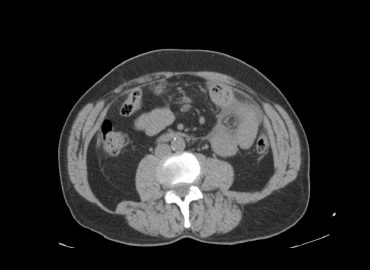

Paciente masculino de 34 años con distensión y dolor abdominal.